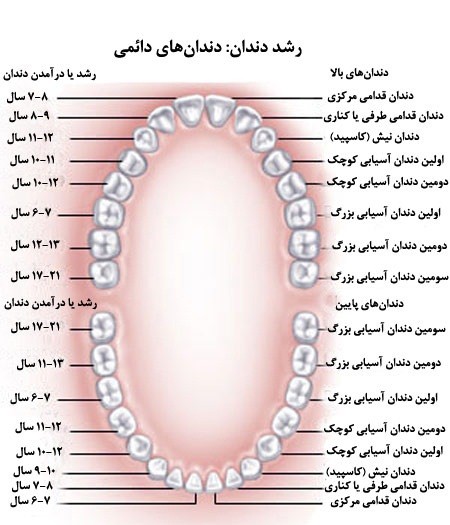

قیمت: 156٬000 تومان - دسته بندی فایل: علوم پزشکیپاورپوینت آناتومی و مورفولوژی دندان

فروش ویژه پاورپوینت حرفه ای آناتومی و مورفولوژی دندان با تخفیف استثنایی فقط 123452 هزار تومان تعداد اسلاید : 217 اسلاید